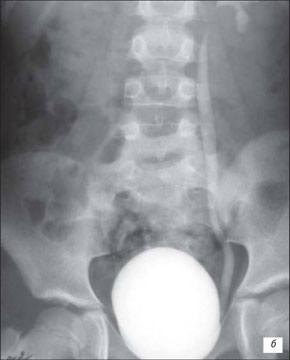

Екскреторна урографія хворого з двостороннім обструктивним мегауретритом

На екскреторній урографії ми спостерігаємо збільшення мисочок, розширення сечоводів, і змінену форму сечового міхура. Стінки якого мають бугристу, нерівну поверхню.